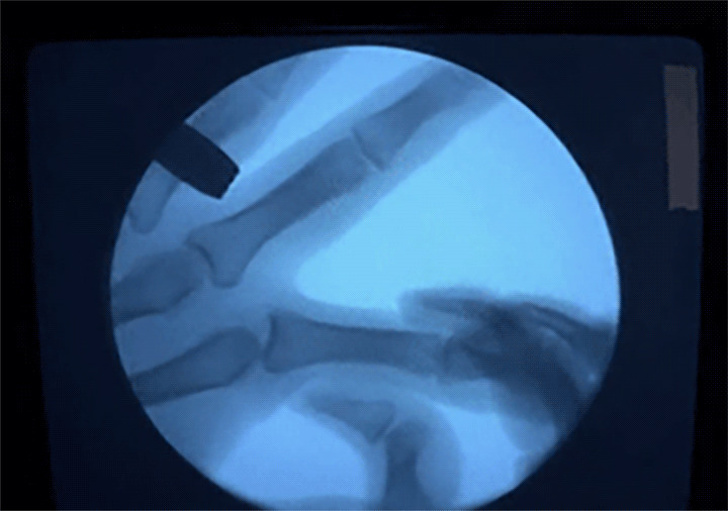

Темна пляма між суглобами праворуч — порожнеча, яка утворюється під час хрускоту.

Багато вчених сходяться на думці, що звук, який з'являється при хрусте пальцями, виникає з-за лопаються бульбашок в синовіальній рідини, що знаходиться між суглобами. Але вони досі не можуть точно пояснити, чому цей хрускіт настільки гучний.

Рідина, яка знаходиться між суглобами, містить кисень, азот і вуглекислий газ. Коли ми розтягуємо суглоби, газ звільняється і з'являються бульбашки, які лопаються. Щоб знову хрустнуть тим же пальцем, необхідно почекати, поки гази рідини не накопичаться знову.

Одне дослідження, в якому було змодельовано процес хрускоту, показує, що гучний звук тільки частково виходить від лопаються бульбашок. Звідки береться інша частина звуку, незрозуміло. Якщо це не суглоб, не бульбашки, то що це може бути?